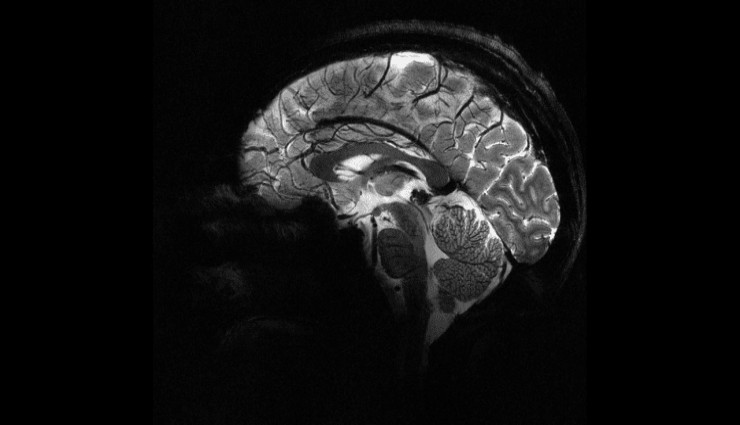

Fransa Atom Enerjisi ve Alternatif Enerjiler Kurumu (CEA), insan beyninin en net görüntüsünü yayınladı. Görüntü dünyanın en güçlü manyetik rezonans görüntüleme (MRI) cihazıyla elde edildi.

TRT Haber‘in aktardığına göre beynin en net görüntüsü ‘Iseult’ adlı MRI cihazıyla çekildi.

CEA’nın açıklamasına göre cihaz 20 gönüllü üzerinde test edildi ve neredeyse 4 dakikada en net beyin görüntüsünün elde edildi.

11,7 Tesla manyetik gücüne sahip Iseult’ın çektiği görüntü, hastanelerde yaygın kullanılan cihazlarla ancak saatler süren çekimle elde edilebilirdi.